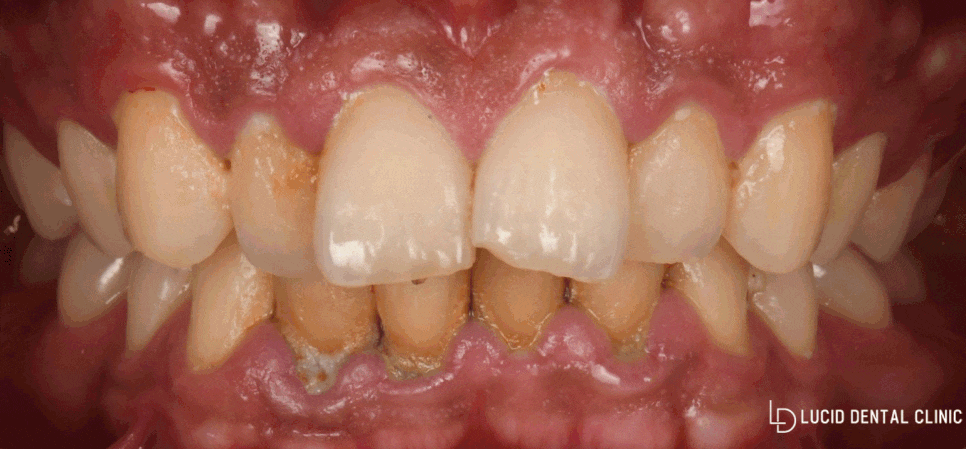

오늘 논현동 치과 에서

소개해 드리는 사례 속 환자께선

치주 질환 및 누렇게 변한 색이

고민이라며 찾아오셨습니다.

곧바로 정밀 구강 검진을 시행한 결과,

아래와 같은 모습을 볼 수 있었습니다.

-

치주 질환으로 잇몸 퇴축

불규칙한 치열

여러 가지 이유로 착색된 치아들

위와 같은 문제들로 인해

충치 질환은 물론, 이시림 증상이 나타나

정상 생활에 방해를 줄 수 있는데요

특히 고르지 못한 치열과 길이, 그리고 착색은

심미적으로 불편감을 줄 수 있습니다.